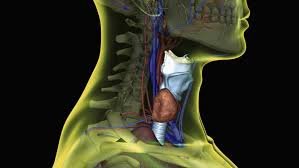

The Stellate Ganglion Block (SGB) is an advanced procedure that targets a nerve cluster in the neck to alleviate pain and reduce stress. Initially used for chronic pain management, it is now gaining recognition as a treatment for PTSD, anxiety, and other stress-related conditions.

SGB involves a precise injection of a local anesthetic near the stellate ganglion, a nerve bundle in the neck. This temporarily blocks pain signals and regulates the sympathetic nervous system, providing fast relief from chronic pain and easing symptoms of anxiety and PTSD.

A precise injection near the stellate ganglion using imaging guidance.

A Stellate Ganglion Block is an injection of local anesthetic near a bundle of nerves in the neck called the stellate ganglion. These nerves influence the body’s sympathetic nervous system, which regulates the fight-or-flight response.